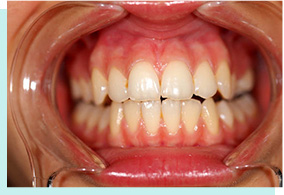

影響發音交流

小鳥嘴被嘲笑

咀嚼功能不健全

清潔難總蛀牙

吃飯塞牙易牙病

牙龈出血頻繁

大小臉易自卑

影響臉型發育